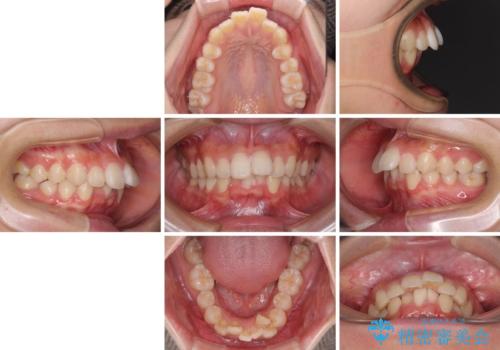

- 前に傾斜して飛び出した上顎前歯を気にして来院された患者様です。

上下前歯の前後差が大きく、下顎前歯が隠れるほど深い咬合で、咬合力が強い状態でした。

口元の突出感を改善するために、上下左右の第一小臼歯4本を抜歯し、ワイヤー装置にて矯正治療を行うこととしました。

深い咬み合わせの改善に時間がかかりましたが、下顎前歯がしっかりと見えるまでに整えることができ、口元の突出感も大幅に改善することができました。